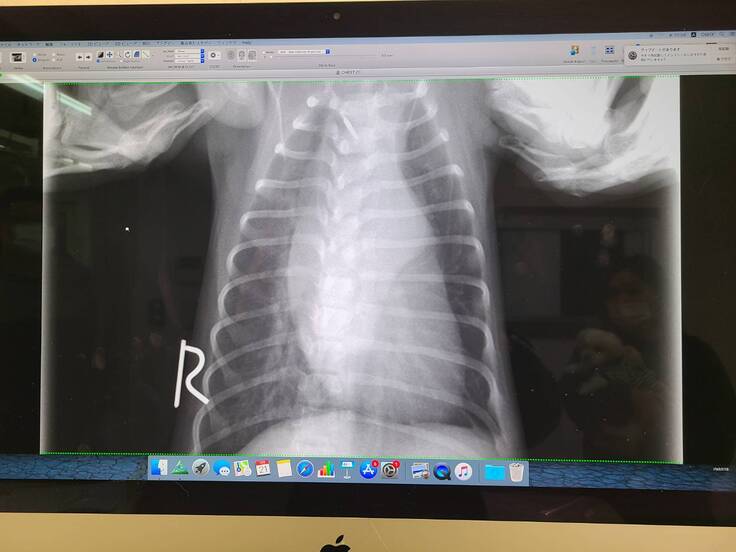

▲そらのレントゲン写真です。

掲載許可はいただいています。